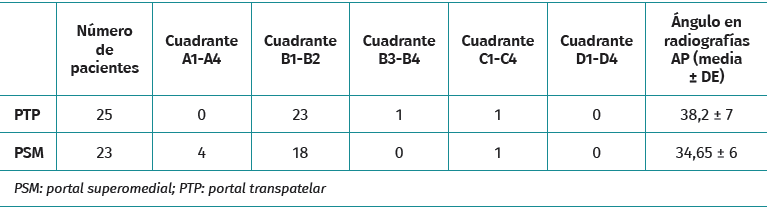

El posicionamiento del TF se evaluó mediante dos proyecciones radiológicas realizadas un mes después de la intervención: una proyección AP y otra de perfil (P) a 30° de flexión. El aparato de rayos Siemens Ysio® S y Siemens Axion Aritos® MX/VX se utiliza a una distancia de 1,5 metros. Las mediciones se realizaron con el programa informático Raim Alma. La proyección coronal permite estudiar la orientación del TF. Se mide el ángulo formado entre la superficie articular bicondilar y el TF. Revisando estudios previos incluidos en la bibliografía, un ángulo menor de 30° o mayor de 55° se asocia con reconstrucciones insuficientes del LCA y mayor riesgo de rotura(10). La vista sagital indica el posicionamiento de la entrada del TF en el área intercondílea femoral externa. Se utiliza el método del “cuadrante femoral”(11) según el cual se toma como referencia la línea de Blumensaat (intercondílea posterior), que sirve de guía para elaborar el eje de coordenadas que se muestra en la Figura 4A.

Perpendicularmente a la línea de Blumensaat y con la superficie articular anterior y posterior como límite, la superficie se divide en 4 espacios de igual longitud. Estos espacios constituyen el eje de abscisas, que se identifican de posterior a anterior con las letras A, B, C y D. El correcto posicionamiento del TF para la inserción femoral del LCA corresponde al área delimitada según este eje de coordenadas del método del cuadrante femoral con los valores B1 y B2 que se muestran en la Figura 4B. El principal resultado radiológico fue la posición del TF, que se llevó a cabo mediante dos proyecciones radiológicas un mes después de la intervención: una proyección AP y una P a 30° de flexión. La proyección AP se utilizó para medir el ángulo formado entre la superficie articular bicondilar.

La proyección sagital se utilizó para determinar la entrada del TF en el área intercondílea femoral externa y se representó mediante coordenadas del método del cuadrante femoral.

Las variables continuas se presentan como media, desviación estándar o error estándar de la media. Las variables categóricas se presentan como frecuencias. La relación entre variables se analizó con tablas de contingencia para las categóricas y la inferencia se estudió con la prueba t de Student para analizar variables cuantitativas y la prueba exacta de Fisher para variables categóricas. Se utilizó la prueba t de Student para la medición angular en la proyección coronal y la prueba exacta de Fisher se usó para estudiar su posicionamiento en la proyección sagital. Shapiro-Wilk se utilizó para las variables cuantitativas que no se distribuyen normalmente. Se realizó un análisis estadístico mediante la prueba de Mann-Whitney (Tablas 1 y 2) para comparar la evaluación clínica y comprobar si existían diferencias significativas en cuanto a la pérdida de función y el dolor en los grupos de PSM y PTP. El nivel de significación se fijó en el 5% (α = 0,05). Los datos se analizaron mediante el programa SPSS 19 (SPSS Inc., Chicago, Illinois).

El PTP dio lugar a una verticalidad del TF marginalmente mayor (38,76 ± 7,04°) en comparación con el PSM (34,65 ± 6,44°; p = 0,041). Sin embargo, una parte de los pacientes de ambos grupos presentaban ángulos del túnel fuera del intervalo óptimo de 30-55°. El posicionamiento axial óptimo del TF en B1/B2 fue más frecuente con el PTP (92 frente a 52%; p = 0,0047) (Tabla 2).